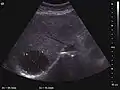

They can be single or multiple, with variable size, generally less than 20 mm (congenital). Rarely, sizes can reach several centimeters, leading up to the substitution of a whole liver lobe (acquired, parasitic). They may be associated with renal cysts; in this case the disease has a hereditary, autosomal dominant transmission (von Hippel Lindau disease).

The ultrasound appearance is a well defined lesion, with very thin, almost unapparent walls, without circulatory signal at Doppler or CEUS investigation. The content is transonic suggesting fluid composition. The presence of membranes, abundant sediment or cysts inside is suggestive for parasitic, hydatid nature. Posterior from the lesion the acoustic enhancement phenomenon is seen, which strengthens the suspicion of fluid mass. They typically displace normal liver vessels but no vascular or biliary invasion occurs.